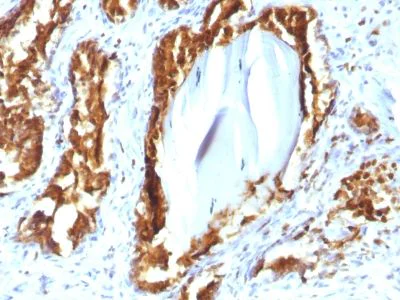

Immunohistochemistry (Formalin/PFA-fixed paraffin-embedded sections) - Anti-PAP antibody [rACPP/1338] (AB238037)

Immunohistochemical analysis Formalin-fixed, paraffin-embedded human Prostate Carcinoma tissue stained for Prostatic Acid Phosphatase using ab238037 at 2 μg/mL (for 30 minutes at RT) (Staining of formalin-fixed tissues requires heating tissue sections in 10mM Tris with 1mM EDTA, pH 9.0, for 45 min at 95°C followed by cooling at RT for 20 minutes).